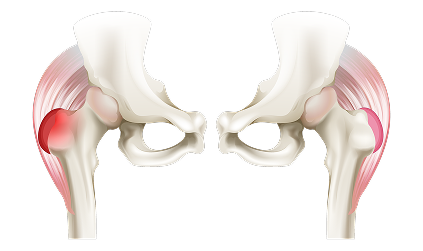

- Muscle-Preserving: Our approach minimizes damage to muscles, allowing quicker recovery.

- Pain-Free Living: Relieves joint pain and discomfort.